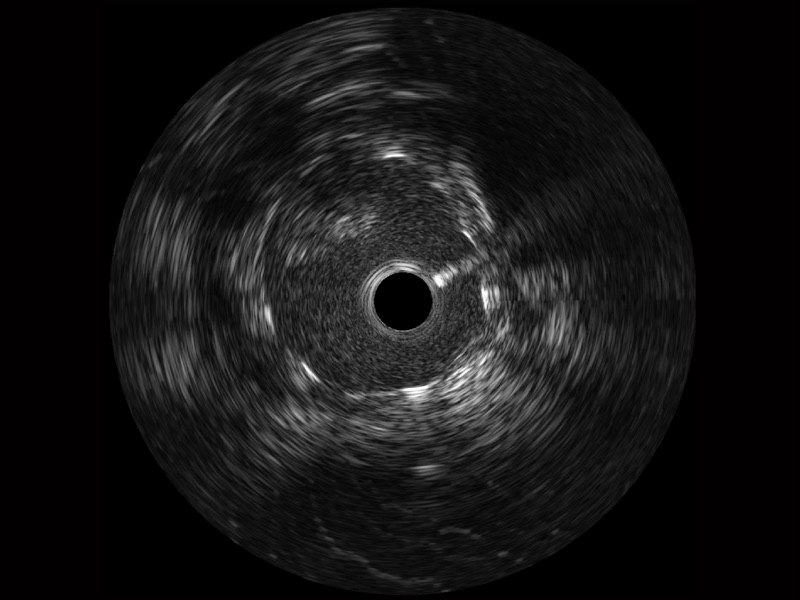

临床图

支架内血栓